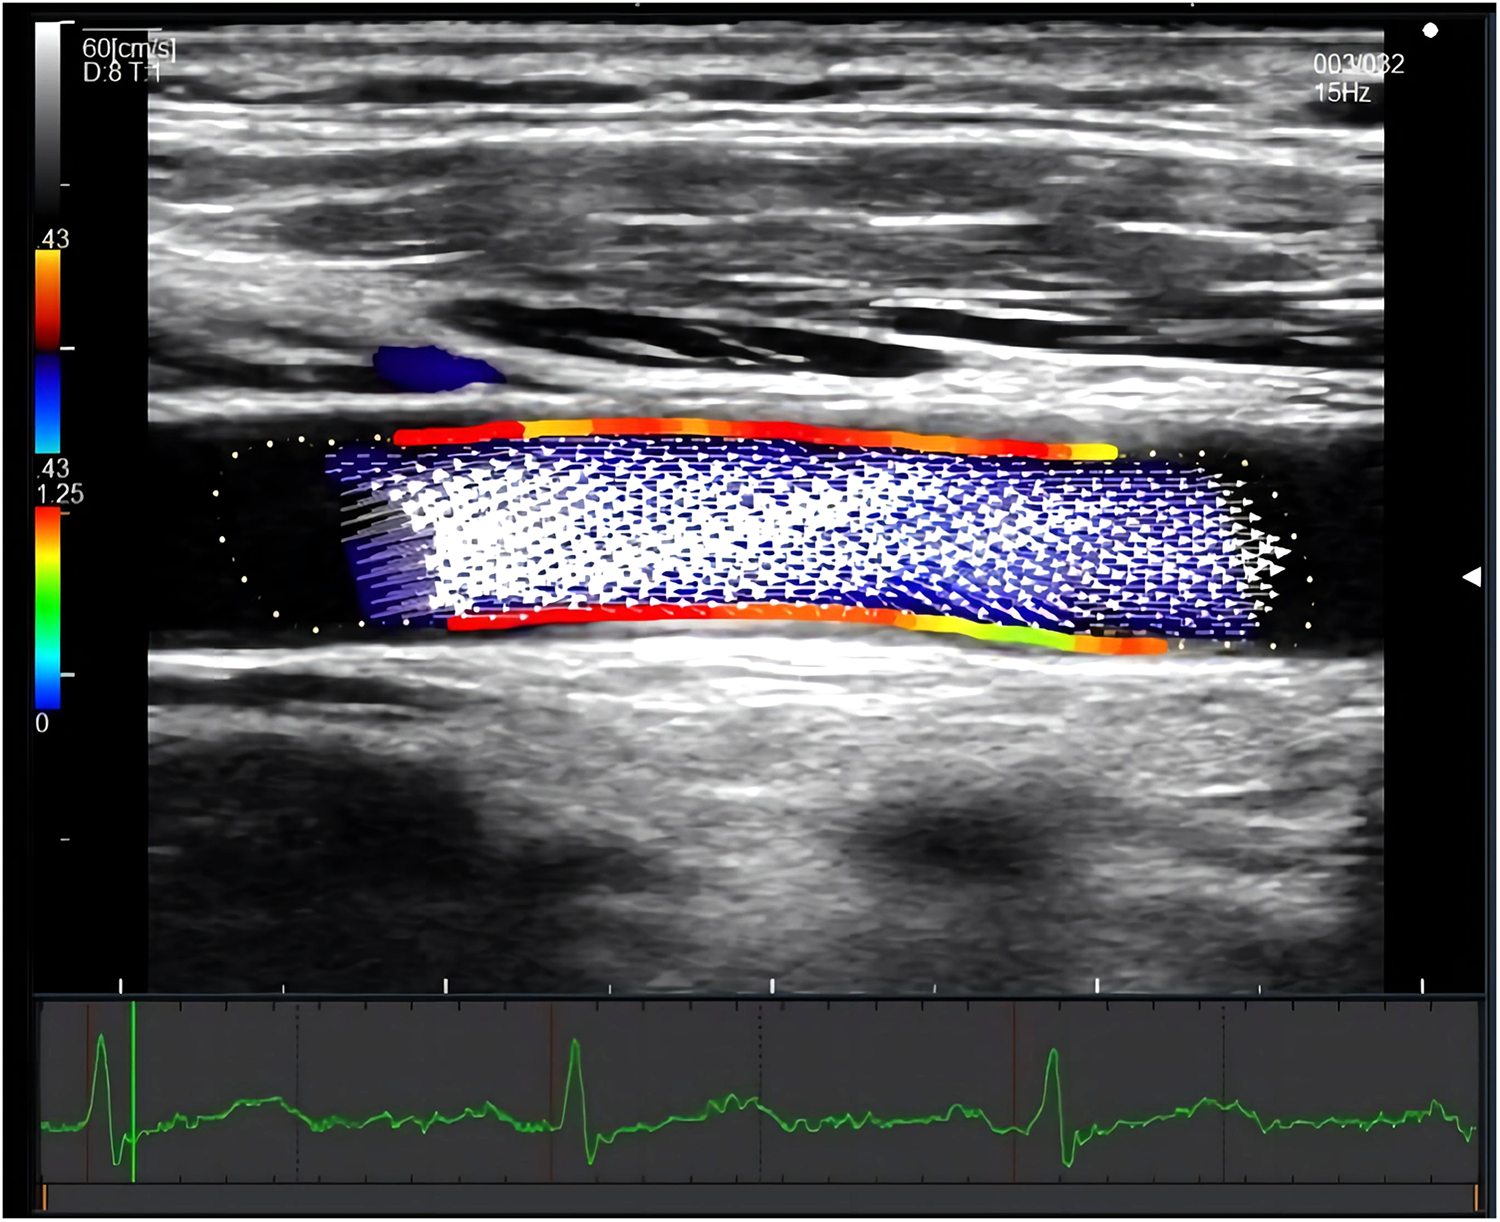

CCA WSS was measured at 1 cm proximal to the bifurcation without plaque in the supine position. If plaque existed at the proximal bifurcation segment, the middle segment of CCA was examined instead. Images of three heartbeats were saved as raw data in each measurement. The depth was controlled to less than 3.5 cm. The steering angle of the color Doppler flow was adjusted from 0 to 30 degrees. The dynamic range and velocity range were kept as small as possible within the aliasing correction, and the gain was adjusted as necessary. The crossbeam was automatically set and was adjusted by 5-degree increments to maximize the crossbeam Doppler signal in the vessel. The unilateral systolic CCA WSS value of the anterior and posterior walls was calculated automatically using DAS-RS1 software (Hitachi, Tokyo, Japan). (Shown in Figure 2) Average systolic WSS was measured by combining the values of bilateral CCA WSS.

Figure 2

Measurement of systolic CCA WSS by VFM technique. The figure showed a longitudinal section of the common carotid artery. The red area indicated a relatively high wall shear stress, and the green area indicated a relatively low wall shear stress. The white arrow represents the blood flow velocity vector of the carotid artery. The electrocardiogram on the bottom ensured the time of measurement.